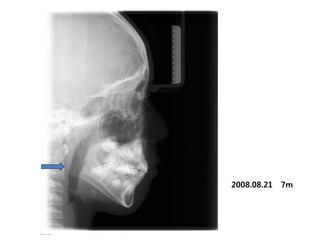

S.H. Jang

1999.10.14/M

C.C

• Max. protrusion

• Lower crowding

Dx

• Mouth breathing, retro-positioned tongue

Goal

• Lip seal(Adenoidectomy and Tonsilectomy)

• Establish tongue posture with T4K

A &T 2008.01 Tr start

2007.11.21

2008.05.08 4m

2008.08.21   7m